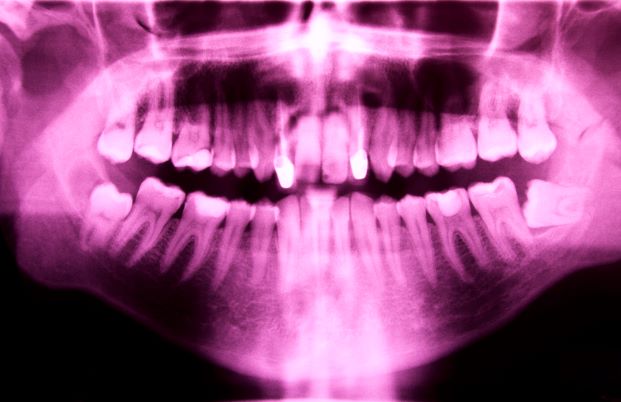

The third molars or wisdom teeth are the last four molars located on each side of the jaws behind the second molars.

These usually appear in humans between 18 and 25 years of age and may never appear, although they can appear at younger ages or later. Sometimes only some of them erupt.

However, as the human species changed its diet, smaller jaws began to develop. That is why you can find wisdom teeth growing in an inappropriate direction or shape today due to lack of space.